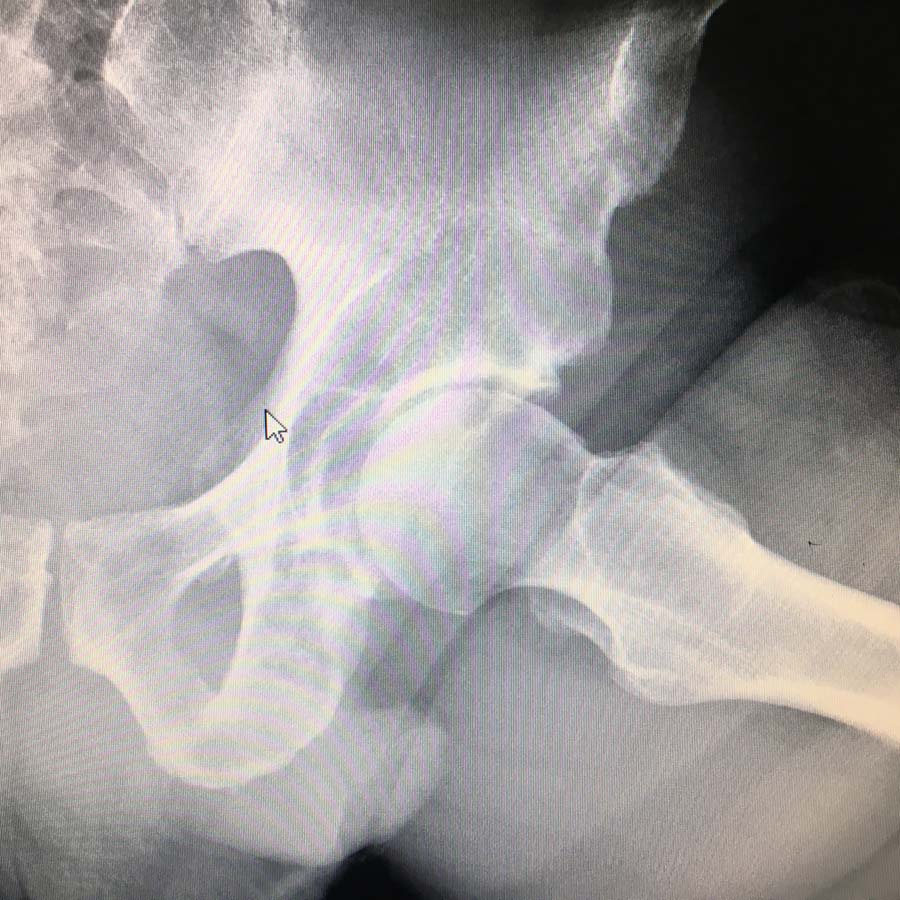

Εικόνες α.β.γ.δ: Απλές ακτινογραφίες δεξιού (α,β) και αριστερού (γ,δ) ισχίου προθιοπίσθιες και σε απαγωγή 45ο με έξω στροφή. Παρατηρείται στένωση του μεσαρθρίου διαστήματος, σκλήρυνση των αρθρικών επιφανειών, κοτύλης και μηριαίας κεφαλής, και ανάπτυξη οστεοφύτων στην έξω περιοχή της κοτύλης.